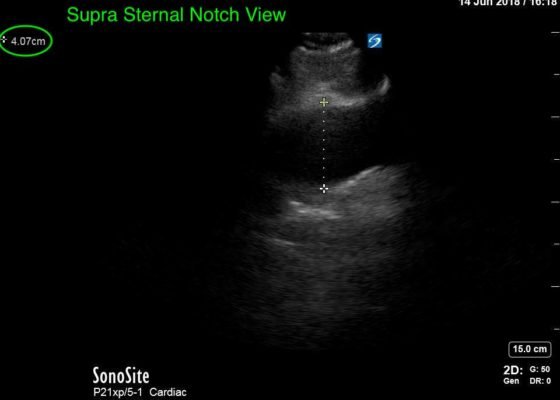

Thoracic Aortic Aneurysm Measured by Point of Care Ultrasound Suprasternal Notch View

DOI: https://doi.org/10.21980/J8Z64VPoint-of-care cardiac echocardiogram demonstrated a dilated ascending aorta (illustrated in red) measuring approximately 4 cm in the parasternal long axis (PLAX). A dilated aortic arch (illustrated in green) also measuring approximately 4 cm was appreciated using the suprasternal notch view (SSNV). A follow-up computed tomography angiogram (CTA) was performed, validating bedside ultrasound measurements.